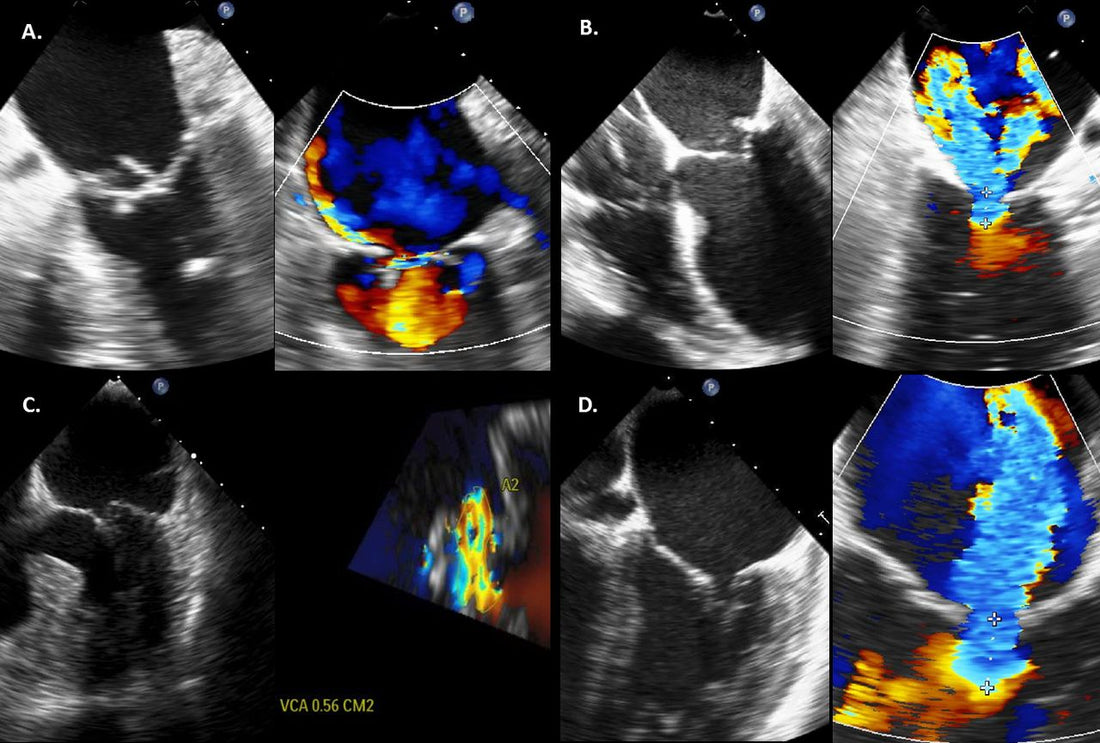

主动脉瓣关闭不全可以通过结合病史评估、体格检查和诊断测试来诊断。这些检查可能包括超声心动图、心电图 (ECG)、胸部 X 光检查和心脏 MRI。这些测试有助于确定病情的严重程度并指导治疗计划。